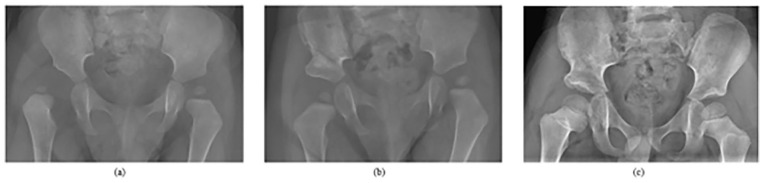

Results: Twenty-three hips (15 patients) were included. Mean age at the time of surgery was 19.6 months (Range: 8.2-36.0 months), and mean follow-up was 4.3 years. The most common connective tissue disorder condition included was Ehlers-Danlos syndrome (13%). A majority of open reductions were performed via an anterior approach (96%). Seven hips (30%) underwent a concomitant pelvic osteotomy without femoral osteotomy and seven hips (30%) underwent both pelvic and femoral osteotomies. Twenty-two hips (96%) were International Hip Dysplasia Institute grade 1 at the final follow-up. Re-dislocation occurred in four hips (17%); eight hips (35%) demonstrated residual acetabular dysplasia, five hips (22%) demonstrated proximal femoral growth disturbance, and nine hips (39%) developed stiffness postoperatively.

Conclusions: Patients with connective tissue disorders and ligamentous laxity have comparable rates of residual acetabular dysplasia, proximal femoral growth disturbance, and (surprisingly) stiffness as typical developmental dysplasia of the hip following open hip reduction surgery. Although the re-dislocation rate in the connective tissue disorders group was approximately 2-3 times higher, the difference did not reach statistical significance. Given that the study was limited by a low sample size, however, it is possible that the findings of no difference in residual acetabular dysplasia and proximal femoral growth disturbance were potentially due to a lack of power.